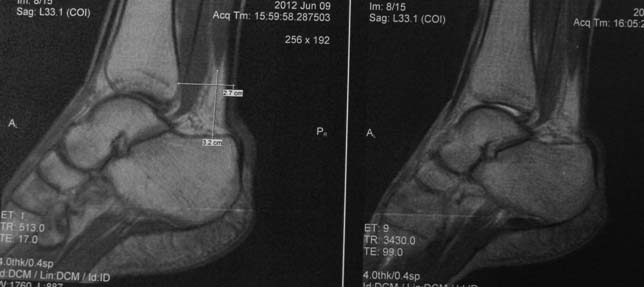

Спасибо всем, кто принимает участие в обсуждении случая. Досылаю рентгенограммы и МРТ. Хотелось-бы уточнить объем резекции пяточных костей.

Вложение не в текстовом формате было извлечено…

Имя     : мрт.jpg

Тип     : image/jpg

Размер  : 36884 байтов

Url     : http://weborto.net:8080/pipermail/ortho/attachments/20120619/3904cc51/attachment-0005.jpg